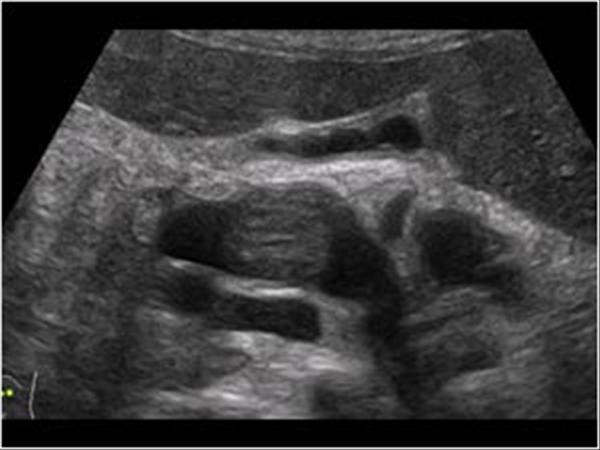

RCC

» Thông tin: Nữ giới – 69 tuổi.

» Lâm sàng: Đái máu.

# Ung thư biểu mô tế bào thận phải (Renal cell carcinoma – RCC) / Huyết khối tĩnh mạch chủ dưới.